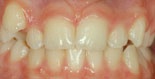

Överbett

överbett före behandling överbett efter behandling

Före behandling av överbett Efter behandling av överbett